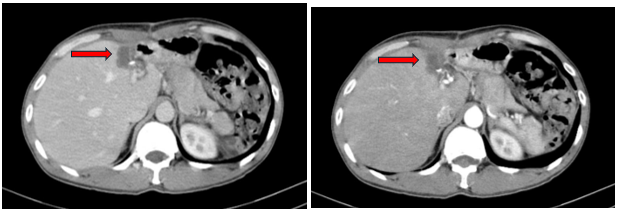

Chụp cắt lớp vi tính ổ bụng sau mổ:

Hình 3: Hình ảnh tụ dịch vị trí diện cắt gan trái sau phẫu thuật (mũi tên đỏ) trên phim chụp CT ổ bụng